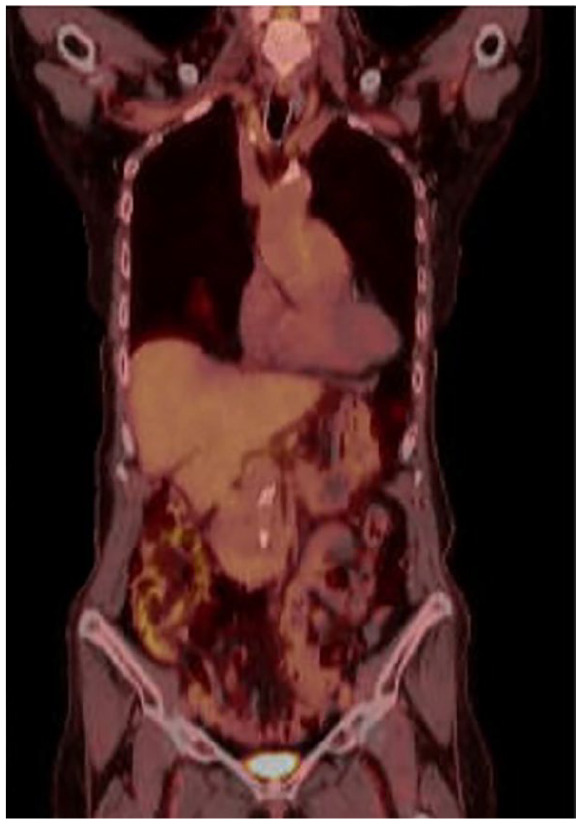

具有错配修复缺陷(dMMR)和微卫星不稳定性高(MSI-H)状态的结直肠癌(CRC)代表了对免疫检查点抑制剂(ICIs)反应良好的高度免疫原性亚群。然而,ICIs在可切除的早期结直肠癌中的作用仍在研究中。我们报告一例81岁的妇女诊断为III期腺癌的右结肠,谁拒绝手术。免疫组化显示MLH1和PMS2缺失,与dMMR一致。肿瘤基因组分析显示MSI-H、高肿瘤突变负担、BRAF V600E和BRCA2突变。种系检测BRCA和Lynch综合征相关突变呈阴性。患者接受新辅助派姆单抗治疗。4个月后,肠系膜淋巴结病变消退,但局灶性结肠增厚持续存在。病人再次拒绝手术。在派姆单抗治疗10个月时,PET/计算机断层扫描和结肠镜检查显示没有残留疾病。她出现了与免疫相关的肾上腺功能不全,用皮质类固醇治疗。该病例显示,在患有体细胞dMMR/MSI-H、BRAF V600E和BRCA2突变的患者中,单抗派姆单抗治疗可切除结肠癌的临床完全缓解。它支持了早期使用icis(在转移进展和免疫逃逸之前)可能提高疗效的假设。该报告强调了在基因选择的结直肠癌患者中,个性化、省去手术的治疗策略的潜力。

Colorectal cancer (CRC) with deficient mismatch repair (dMMR) and microsatellite instability-high (MSI-H) status represents a highly immunogenic subset that responds well to immune checkpoint inhibitors (ICIs). However, the role of ICIs in resectable, early-stage CRC remains under investigation. We report the case of an 81-year-old woman diagnosed with stage III adenocarcinoma of the right colon, who declined surgery. Immunohistochemistry revealed loss of MLH1 and PMS2, consistent with dMMR. Tumor genomic profiling demonstrated MSI-H, high tumor mutational burden, BRAF V600E, and BRCA2 mutation. Germline testing was negative for BRCA and Lynch syndrome-associated mutations. The patient was treated with neoadjuvant pembrolizumab. After 4 months, mesenteric lymphadenopathy resolved, but focal colonic thickening persisted. The patient again declined surgery. At 10 months of pembrolizumab therapy, PET/computed tomography and colonoscopy showed no residual disease. She developed immune-related adrenal insufficiency, managed with corticosteroids. This case demonstrates complete clinical remission of resectable colon cancer with pembrolizumab alone in a patient with somatic dMMR/MSI-H, BRAF V600E, and BRCA2 mutations. It supports the hypothesis that early use of ICIs-prior to metastatic progression and immune escape-may enhance efficacy. This report highlights the potential for personalized, surgery-sparing treatment strategies in genomically selected CRC patients.